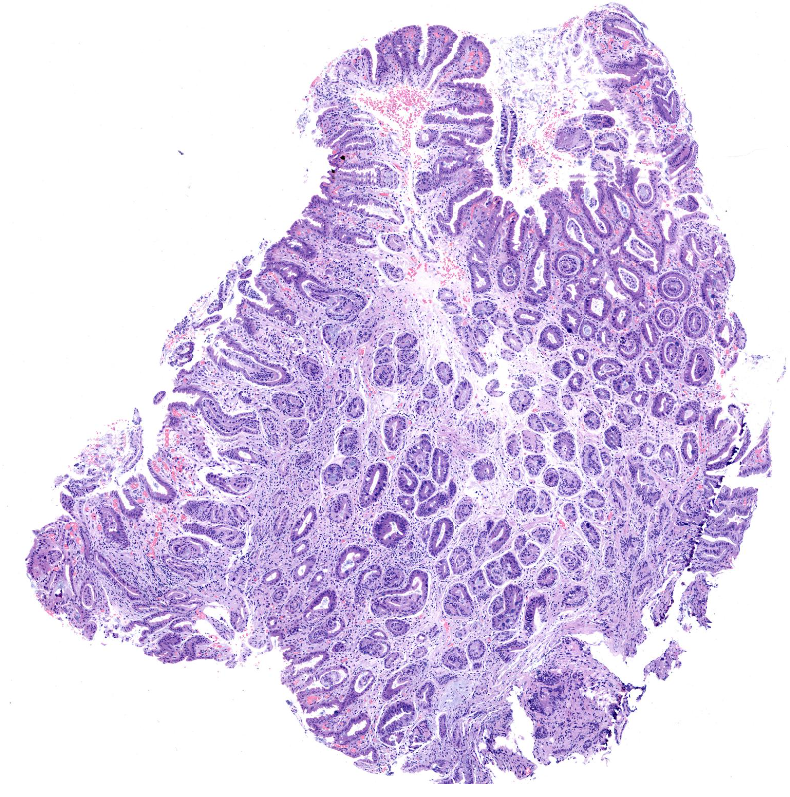

胃窦体交界表浅平坦病变

胃窦体交界活检

窦体交界表浅平坦病变1*1.2cm.

标记排除高级别

倾向炎症反应性增生

慢性炎症,伴有肠化。

高瘤

深切之后局灶高瘤

高级别

高瘤变。